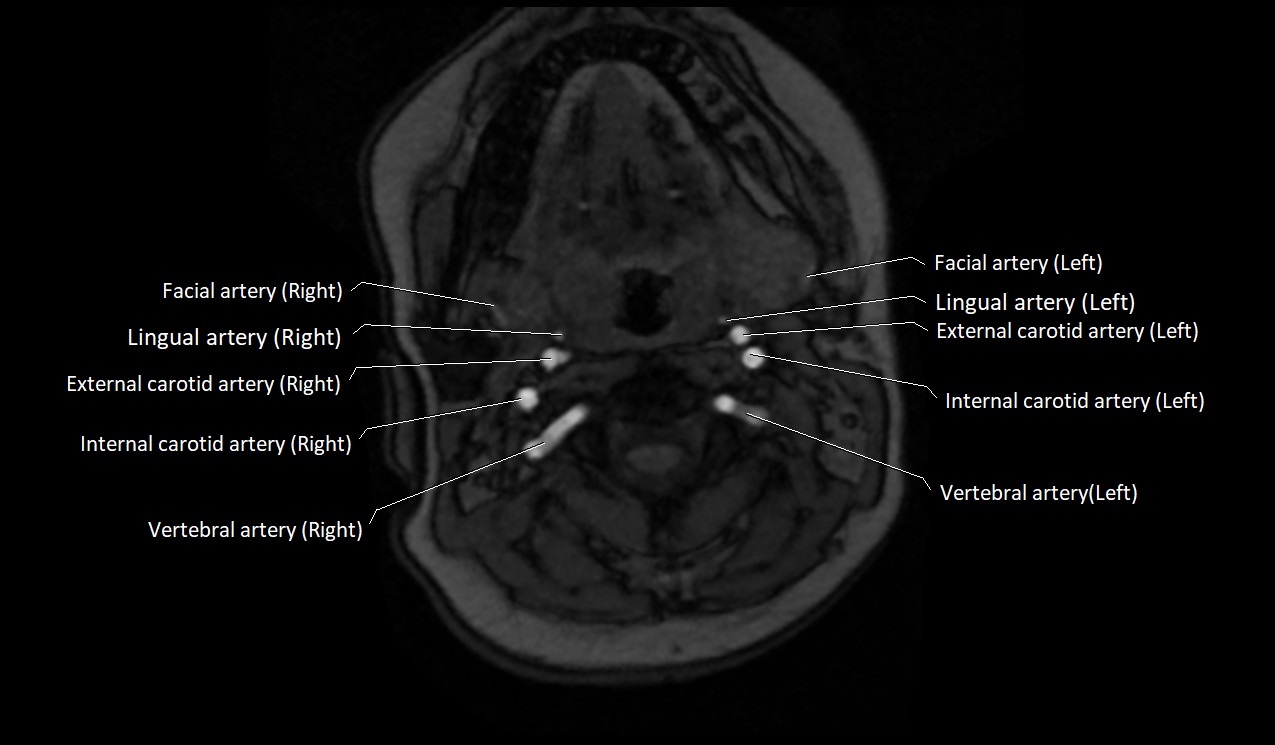

MRI images

image